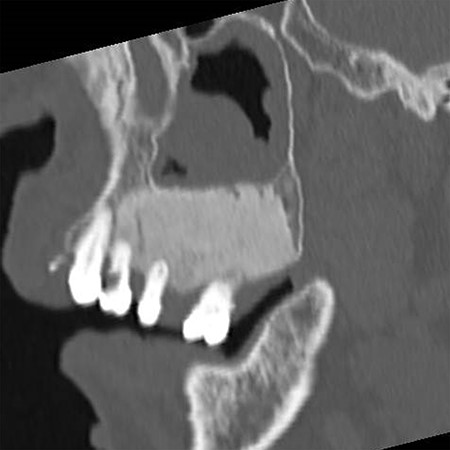

Sagittal section of CT image showing the maxillary bone with a ground glass appearance in distal regions from #24 part and bone resorption around #25 and #26.

A 69-year-old woman was referred to our hospital by a dentist at another hospital because of swelling in her left maxilla. There was the mobility of the left maxillary second premolar and first molar (FDI #25 and #26) and swelling of the surrounding gingiva. Computed tomography (CT) images revealed maxillary bone expansion with a ground glass appearance (Fig. 1). The patient had begun steroid therapy for polymyalgia rheumatica 4.5 years earlier. Since then she had been taking alendronate, one of the oral BPs, for the prevention of glucocorticoid-induced osteoporosis.